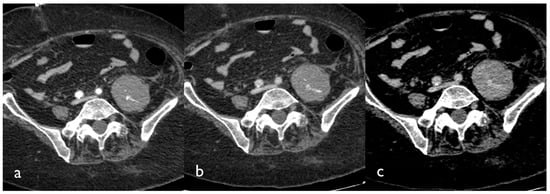

If active bleeding occurs within a hematoma with fluid–fluid level, it could be possible to identify the “signal flare” sign, which is generated by the layering of extravasated contrast medium between cellular and fluid components of the hematoma, due to the different gravitational weight (Figure 2) [15].

Figure 2. CT images of a patient presenting with a large hematoma of the left iliopsoas muscle. Tri-phase contrast-enhanced axial CT images show contrast blush in the arterial (a), portal (b), and delayed phase (c); active bleeding is seen like small hyperdense foci within the hematoma that appear in the arterial phase and grow in the venous and delayed phase.